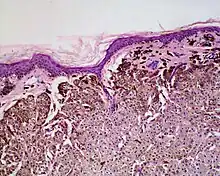

Histologically it is characterized by swollen, pale, polyhedral melanocytes, with pale cytoplasm and a central nucleus.[2] It is different to balloon cell melanoma,[3] which has larger nuclei and is structured like a melanoma.[1]